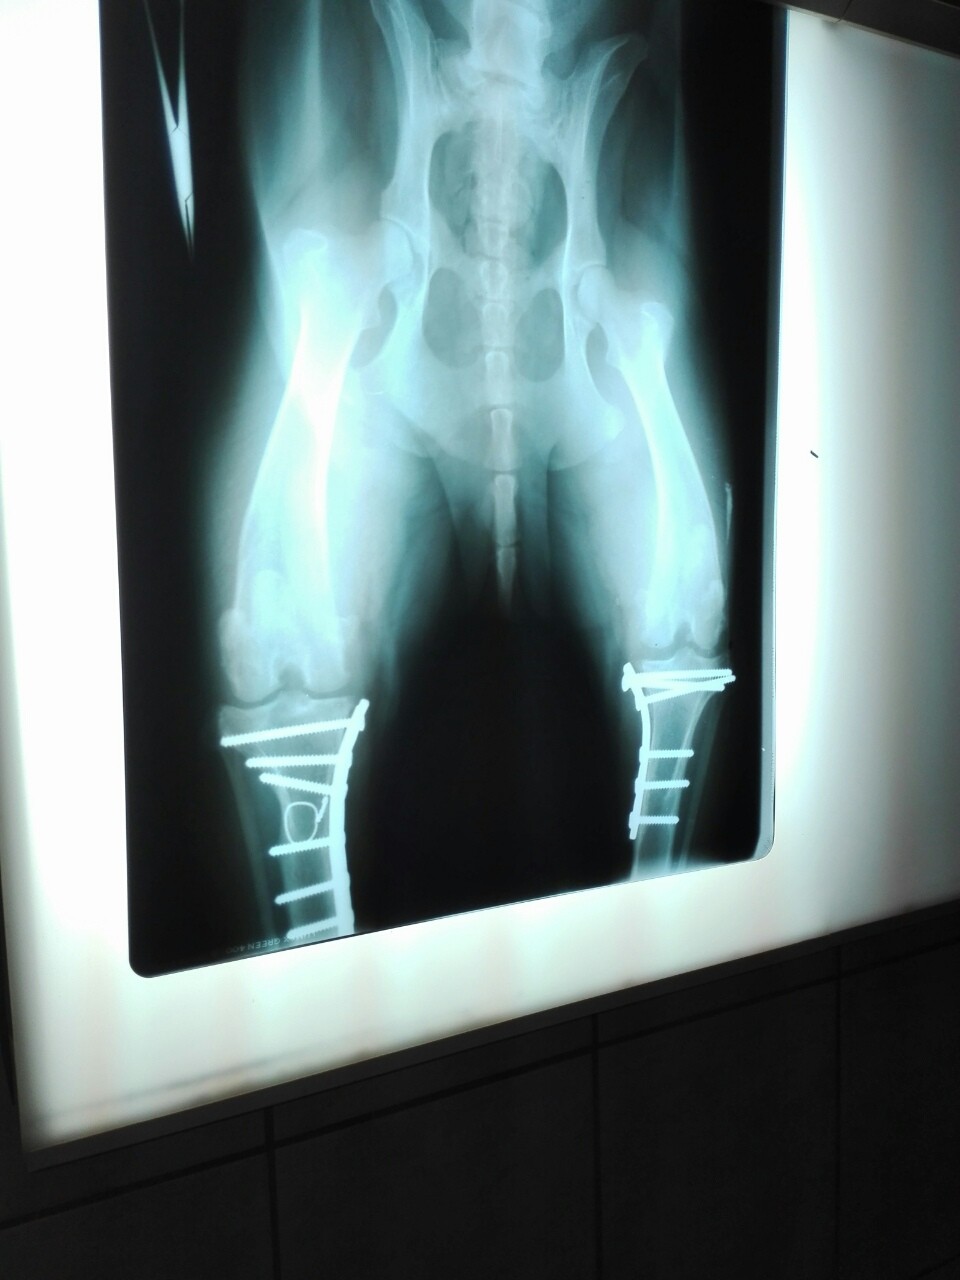

Rosszcsontnak mind a két hátsó lába műtve volt még mielőtt hozzám került, és sajnos most a bal hátsó lába műtétre szorul, mert a szervezetének kezd nemtetszeni az implantátum, sipoly van a lábán, és tegnap már nem tudott ráállni. Sajnos diszplázia is van.

Azt beszéltük a dokival, hogy érdemesebb lenne egyszerre kiszedni mind a kettőt, hogy ne kelljen 2x nekiállni a műtétnek, mert a röntgenfelvétel alapján szerinte csak idő kérdése, hogy mikor kell azt is eltávolítani.